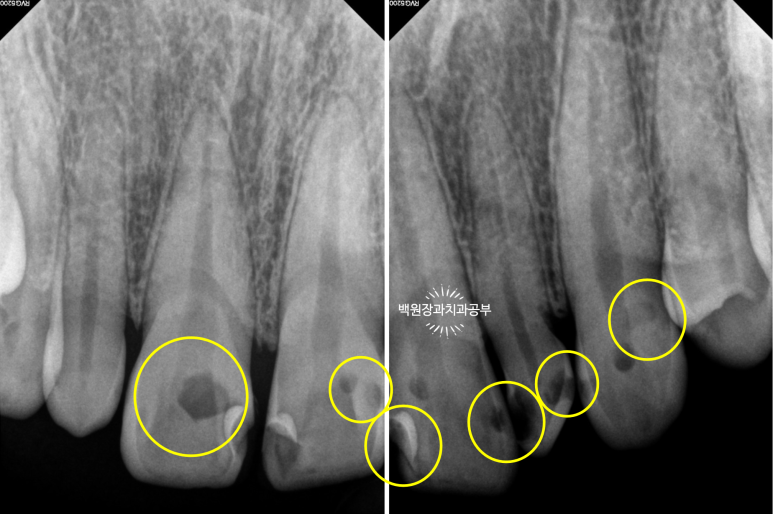

얼마나 충치가 진행되었는지 눈으로만 확인하지 않습니다.

치근단 사진을 촬영하여 보다 자세히 살펴볼 수 있었습니다.

눈으로 보는 것과 같은 위치입니다만, 엑스레이로 보았을 때 현재 위치하는 충치가 치아 내부의 신경관과 얼마나 가까이 위치하는지를 확인할 수 있었습니다.

이에 가장 충치가 심했던 측절치는 신경치료를 할 가능성이 아주 높으며 기둥을 설치해야 한다는 정보를 얻을 수 있었습니다.

신경치료가 완료되면 해당 치아속의 재료는 방사선 사진 상 하얗게 표시되게 됩니다.

신경치료 완료 후 남은 치아가 너무 적은 경우에는 치아 내부에 기둥 (=포스트)를 설치하게 됩니다.

눈에 보이는 부분의 치아가 너무 적으니 내부에서라도 힘을 얻으려는 노력이지요.